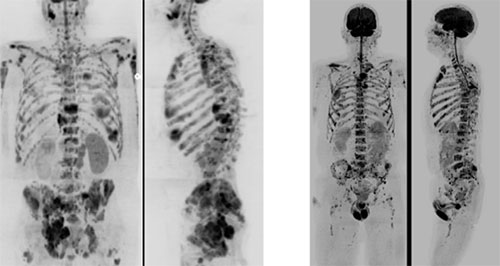

Figure 1: Left 2 panels: 2010. Maximum Intensity Projections (MIP; inverted grey scale) of Whole body b800 DWI in the anterior and lateral projections of a 78-year-old man with progressive multiple myeloma. For three stations, the imaging time was about 20 minutes, and so the examination was focused from the skull base to the lower pelvis. Note the slight imaging intensity variation between the stations. Right 2 panels: 2024. MIP of WB b900 DWI in the anterior and lateral projections of a 66-year-old man with a new diagnosis of multiple myeloma. For six imaging stations from the vertex to the distal thighs, the imaging time is 7 minutes using deep learning reconstruction methods. Note the increased body coverage, more even signal intensity between stations, uniform soft tissue signal, and increased image sharpness.

In 2004, Taro Takahara et al. introduced the concept of Whole-Body Diffusion-weighted Imaging with Background Body Signal Suppression (DWIBS). This technique utilized free breathing, short-tau inversion recovery (STIR) for fat suppression, and high-resolution 3D displays to obtain WB-DWI. Initially, patient table movements were done manually. This innovation, combined with significant improvements in MRI hardware, including modern 1.5-T and 3-T units with echo-planar and parallel imaging capabilities, higher-performance gradients, phased-array multichannel surface coils, and continuous moving table technology, slice-by-slice shimming techniques markedly improved image quality and anatomic coverage, making WB-DWI feasible for wider clinical investigations (Figure 1). The advent of dedicated workstation software also streamlined the viewing and interpretation of whole-body datasets. The driving force behind the accelerated adoption of WB-DWI was not only its technical promise but also compelling clinical needs, which drove the standardization of diffusion imaging approaches (Padhani, et al., 2009) and whole-body MRI applications (Padhani, et al., 2017) (Messiou, et al., 2019). For the most recent developments in WB-DWI, which include the drafting of guidelines for the technique's implementation in various tumor types, the validation of the prognostic role of the criteria, integration with other diagnostic modalities, and the implementation of deep learning and artificial intelligence, please refer to the Timeline section.

The integration of Artificial Intelligence (AI) is significantly reducing WB-DWI acquisition times by more than 50% without compromising accuracy, allowing for faster scans and extended protocols, such as full head-to-feet coverage (Figure 1).